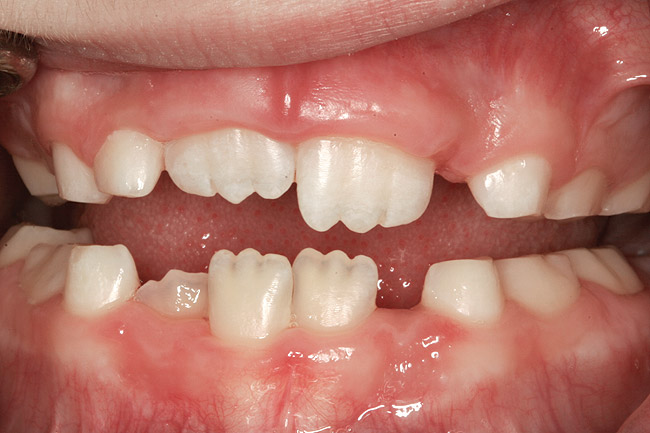

(10.) Narrow maxilla with tooth wear and bilateral crossbite.

Figure 10